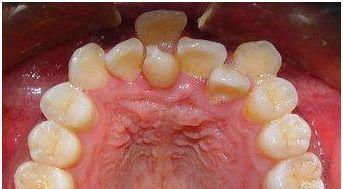

▍ 异常1:双排牙(乳牙滞留)

第一种情况是双排牙齿。简而言之,恒牙已经出来接管了,但是乳牙却没有按时掉落。专业术语是“乳牙滞留”。

简单的乳牙滞留,如下图所示,只需要拔出乳牙并观察恒牙的调整即可。右下方的情况非常严重。下排的恒牙太高,影响整个咬合结构和牙龈健康。两个上切牙的萌出位置也不利于将来的牙周健康,需要及时干预。